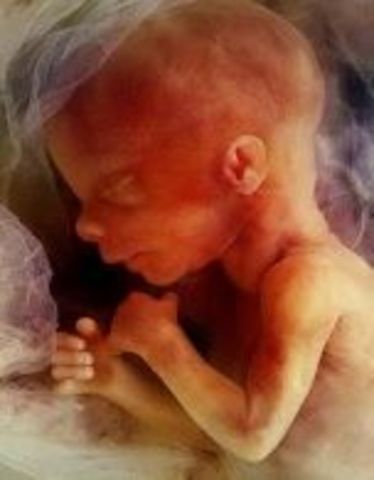

• week 10

week 10

Its now a fetus. muscles are being developed.

• week 11

week 11

Cartilage now calcifying to become bone. Taste buds are starting to develop.

• week 12

week 12

May be able to hear heartbeat. Fetus starts moving spontaneously.

• week 13

week 13

Baby can open and close its mouth. Starts flexing its arms and kicking its legs.